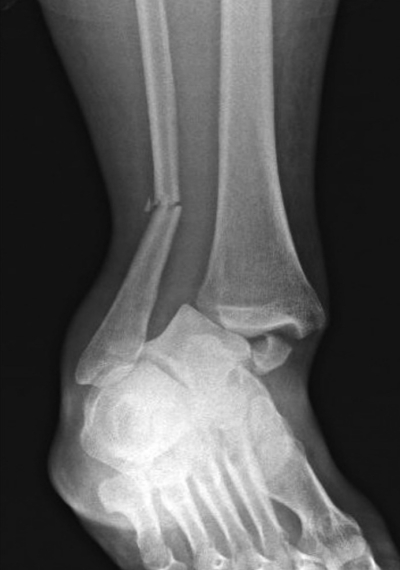

搬入時(受傷2時間後)の意識は清明。体温 36.9 ℃、心拍数 100/分、整。血圧 124/76 mmHg。呼吸数 14/分。SpO2 100 %(鼻カニューラ 1L/分酸素投与下)。右足関節全体に腫脹と圧痛を認める。右足関節周囲に開放創はない。足背動脈は左右差なく触知可能であり、右足趾の自動屈曲伸展運動は可能で、感覚に異常を認めない。右足関節以外に異常を認めない。右足関節単純エックス線写真を別に示す。